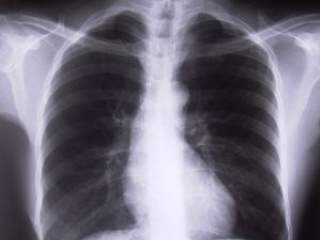

Kada u organizam ne unesemo dovoljnu količinu vazduha, pre svega mislimo na kiseonik, naša krv ne biva oksigenizovana. Proces disanja predstavlja razmenu gasova i oksigenaciju krvi. Kada naš respiratorni sistem ne fnkcioniše kako treba, ceo organizam počinje da pati.